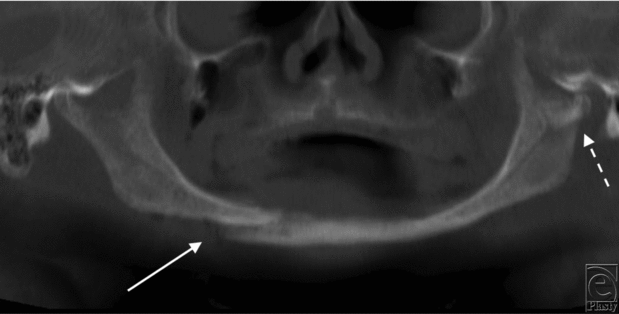

A 66 year-old man presented to a level 1 trauma center following a motor vehicle rollover. He had loss of consciousness and complained of pain in his lower jaw. After the initial trauma resuscitation, panoramic radiograph imaging (Fig 1) and maxillofacial computed tomography were done (Figs 2a and 2b).

| Figure 1. Preoperative panoramic radiographic imaging indicating a right mandibular body (solid arrow) and left subcondylar (dashed arrow) fractures in an edentulous mandible. |

Fractures of the edentulous mandible pose unique challenges. The atrophic mandible has little osteogenic potential and a reduced healing capacity (Figs 1, 2a, and 2b). In the past, MMF was used by wiring the edentulous mandible to dentures or splints. However, because these patients are often elderly with comorbidities, it created additional complications such as infection and pulmonary issues. Transfacial (Figs 4a and 4b) versus transoral approaches for edentulous mandible fractures differ in their advantages and disadvantages. Currently, there is no consensus on optimal treatment regimens for fractures of the edentulous mandible. Treatment should be individualized to each patient.5 Rigid, internal fixation is frequently performed in these patients (Fig 4a). This has led to reduced convalescence time and a more manageable healing process. Primary bone grafting is commonly done because of the atrophic nature of the mandible. Options for ORIF include the use of miniplates (Fig 4b) or larger locking reconstruction types (Fig 4a). Miniplates are small in size, which allows for smaller incision sites. The screws are also small, which allows these plates to be placed in areas of thin bone fragments, such as in the edentulous mandible. Both single and double miniplates can help with load sharing in mandibular fractures. For larger fractures, heavier, load-bearing locking plates can be used. This helps with flexion in the mandible that occurs with opening and closing the mouth, which especially affects the edentulous mandible.